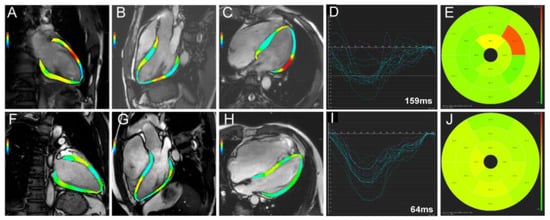

2.3. Cardiac Magnetic Resonance

- Xu, J.; Yang, W.; Zhao, S.; Lu, M. State-of-the-art myocardial strain by CMR feature tracking: Clinical applications and future perspectives. Eur. Radiol. 2022, 32, 5424–5435. [Google Scholar] [CrossRef] [PubMed]

- Song, Y.; Li, L.; Chen, X.; Ji, K.; Lu, M.; Hauer, R.; Chen, L.; Zhao, S. Left Ventricular Longitudinal Dyssynchrony by CMR Feature Tracking Is Related to Adverse Prognosis in Advanced Arrhythmogenic Cardiomyopathy. Front. Cardiovasc. Med. 2021, 8, 712832. [Google Scholar] [CrossRef]

- Taylor, A.J.; Elsik, M.; Broughton, A.; Cherayath, J.; Leet, A.; Wong, C.; Iles, L.; Butler, M.; Pfluger, H. Combined dyssynchrony and scar imaging with cardiac magnetic resonance imaging predicts clinical response and long-term prognosis following cardiac resynchronization. Europace 2010, 12, 708–713. [Google Scholar] [CrossRef]

- Larsen, C.K.; Smiseth, O.A.; Duchenne, J.; Galli, E.; Aalen, J.M.; Lederlin, M.; Bogaert, J.; Kongsgaard, E.; Linde, C.; Penicka, M.; et al. Cardiac Magnetic Resonance Identifies Responders to Cardiac Resynchronization Therapy with an Assessment of Septal Scar and Left Ventricular Dyssynchrony. J. Clin. Med. 2023, 12, 7182. [Google Scholar] [CrossRef] [PubMed]

- Song, Y.; Chen, X.; Yang, K.; Dong, Z.; Cui, C.; Zhao, K.; Cheng, H.; Ji, K.; Lu, M.; Zhao, S. Cardiac MRI-derived Myocardial Fibrosis and Ventricular Dyssynchrony Predict Response to Cardiac Resynchronization Therapy in Patients with Nonischemic Dilated Cardiomyopathy. Radiol. Cardiothorac. Imaging 2023, 5, e220127. [Google Scholar] [CrossRef] [PubMed]